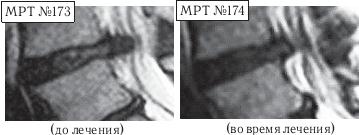

На МРТ № 168 наблюдается состояние поясничного отдела позвоночника: секвестрированная грыжа межпозвонкового диска в сегменте LIV-LV с разрывом задней продольной связки, отрывом фрагмента секвестра с его дорсальной миграцией, абсолютный стеноз спинномозгового канала. Такое состояние — последствия лечения протрузии межпозвонкового диска с применением хиропрактической техники манипуляций на позвоночнике (мануальная терапия). На МРТ № 169 — состояние поясничного отдела позвоночника после лечения методом вертеброревитологии: отсутствие грыжи межпозвонкового диска в сегменте LIV-LV, отсутствие стеноза спинномозгового канала. Разные люди, разные случаи. В следующем примере столь значительное ухудшение состояния здоровья пациента было спровоцировано его индивидуальными занятиями на приспособлении для вытяжения позвоночника. А всё началось с банального желания избавиться от «стартовых» болей в пояснице. ![]() На МРТ № 170 наблюдается состояние поясничного отдела позвоночника: ретроспондилолистез LV (соскальзывание позвонка относительно другого позвонка), протрузии межпозвонковых дисков в сегментах LII—LIV и LIV-LV На МРТ № 171 наблюдается состояние поясничного отдела позвоночника: ретроспондилолистез LV увеличение протрузии межпозвонкового диска в сегменте LIII-LIV, образование секвестрированной грыжи межпозвонкового диска в сегменте LIV-LV с разрывом задней продольной связки, абсолютный стеноз на этом уровне. На МРТ № 172 — состояние поясничного отдела позвоночника в середине первого курса лечения методом вертеброревитологии (после двух недель от начала лечения): наблюдается положительная динамика, выраженная ретрузия секвестра грыжи межпозвонкового диска в сегменте LIV-LV, визуально прослеживается увеличение высоты межпозвонкового диска в том же сегменте, что свидетельствует о начавшемся активном процессе его восстановления, значительное уменьшение стеноза спинномозгового канала на данном уровне. «Стартовые» боли в пояснице в основном проявлялись, когда данный человек выходил из автомобиля. В течение нескольких минут они ему «мешали распрямить спину». Потом, правда, исчезали и могли вновь напомнить о себе после длительного сидения в кресле или в автомобиле. Но так как пациент в силу своих служебных обязанностей вынужден много сидеть (проводить многочасовые совещания, работать с бумагами и так далее), то, естественно, эти боли его раздражали. Как говорится, чрезмерная бюрократия вредна не только для здоровой экономики страны, но и для здоровья самого бюрократа. После того как ему сделали снимок (МРТ № 170) и выяснили, что данные боли возникают вследствие развития спондилолистеза, то, естественно, пациенту предложили операцию с целью стабилизации поражённого сегмента. Не поверив нашим эскулапам (нет пророка в своём Отечестве), пациент отправился в знаменитую клинику за границу, где «светилы» зарубежной медицины (в основном наши бывшие соотечественники) также подтвердили необходимость в оперативном разрешении данной ситуации. Однако пациент, хотя досконально и не разбирался в вопросах заболеваний позвоночника, но зато умел делать выводы из чужих ошибок. Менее двух лет назад его коллега после операции на позвоночнике (кстати, в той же зарубежной клинике) променял солидную должность и кресло «большого начальника» на инвалидность, поэтому этот человек оперироваться не стал и решил пойти другим путём. Приехав домой, он начитался различной рекламы по лечению остеохондроза и его осложнений и выбрал для себя наиболее удобный способ лечения, который вполне устраивал его в режиме служебной деятельности. Обратившись в специализированный медицинский центр по лечению остеохондроза, он приобрёл там специальное приспособление для вытяжения позвоночника и получил от специалистов данного центра комплекс упражнений на нём. Месяц добросовестных тренировок, совмещённых с вытяжением позвоночника (согласно рекомендациям специалистов!) дал свои закономерные результаты. «Стартовые» боли в пояснице при подъёме, из-за которых и началась вся эта история, пациента уже не волновали, поскольку он вообще перестал не только сидеть, но даже ходить. Естественно, начались и другие проблемы в позвоночнике. Следующий месяц в стационаре неврологии (в хирургию упорно не хотел) дали положительные результаты: острые боли постепенно утихали от воздействия сильных обезболивающих препаратов. Пациент смог вставать на ноги, с посторонней помощью проходить от пяти до десяти метров. Сделали снимок (МРТ № 171), на котором выявили секвестрированную грыжу межпозвонкового диска в сегменте LIV—LV с разрывом задней продольной связки. До этого времени ему не могли провести обследования из-за некупируемых болей, а от наркоза он отказывался. Врачи диагностического центра, проводившие МРТ-обследование, посоветовали ему обратиться ко мне. В этот же день, когда больного привезли ко мне на приём, я взялся за эту работу. Через две недели лечения методом вертеброревитологии данный пациент смог самостоятельно приезжать на автомобиле (за рулём). По своей инициативе он сразу сделал ещё одно МРТ (результат интересный, МРТ № 172), на котором можно наблюдать процесс обратного движения грыжи, то есть когда фрагменты выпавшего межпозвонкового диска «заходят» обратно в межпозвонковый диск. Другими словами — процесс ретрузии секвестра грыжи межпозвонкового диска в сегменте LIV-LV а также активный процесс восстановления самого диска. ![]() На МРТ № 173 (увеличенный фрагмент МРТ,№ 171) наблюдается секвестрированная грыжа межпозвонкового диска в сегменте LIV-LV с разрывом задней продольной связки, абсолютный стеноз на этом уровне. На МРТ № 174 (увеличенный фрагмент МРТ № 172) наблюдается состояние межпозвонкового диска в середине первого курса лечения методом вертеброревитологии (после двух недель от начала лечения): положительная динамика, выраженная ретрузия секвестра грыжи межпозвонкового диска в сегменте LIV-LV Вот ещё одни снимки МРТ другого пациента, которые наглядно демонстрируют процесс ретрузии грыжи диска. ![]() На МРТ № 175 наблюдается состояние поясничного отдела позвоночника: компенсированная протрузия, грыжа Шморля в сегменте LIV-LV, спондилёз, гипертрофия задней и передней продольных связок, грыжа межпозвонкового диска сегменте LV—SI, стеноз спинномозгового канала. |